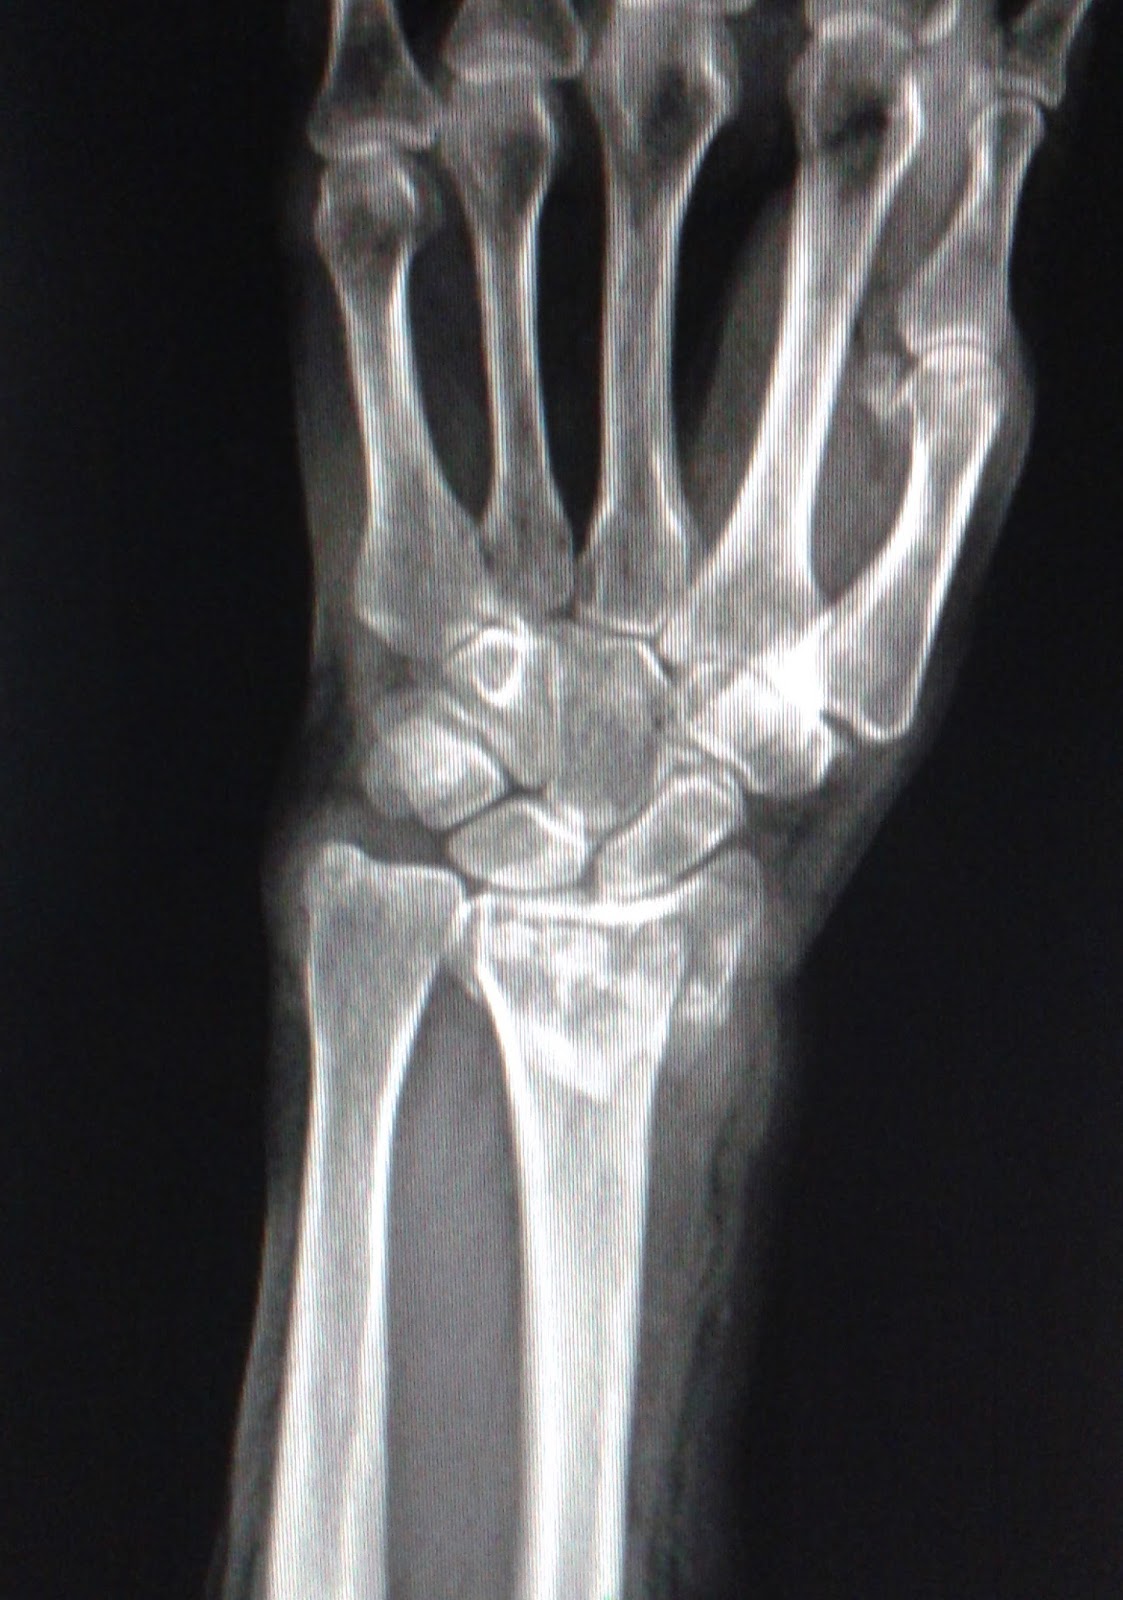

DICAS DE RADIOLOGIA Tudo Sobre Radiologia IMAGENS RADIOLÓGICAS FRATURA DO RÁDIO FRATURA

DICAS DE RADIOLOGIA IMAGENS RADIOLÓGICAS FRATURA DISTAL DO RÁDIO FRATURA DE COLLES